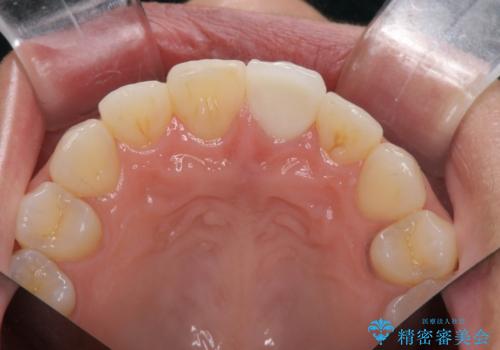

すり減った前歯の形態回復

- すり減ってしまった前歯の審美性の回復を希望され来院されました。

何度かレジン修復を試みたものの、脱離しやすく変色も気になる、とのことでセラミッククラウンによる審美性の回復を計画します。

右側は、クラウンにせず可及的に形態を整えることのみでの対応としました。

自然な色調のセラミッククラウンで審美性を回復することができ、大変満足いただけました。